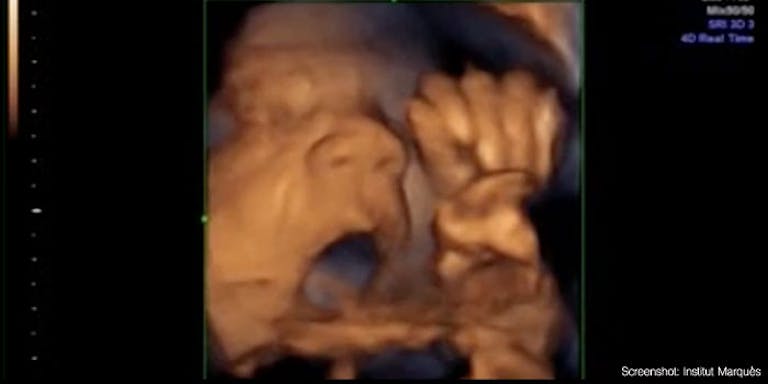

In its 2015 study, the Institut captured preborn babies appearing to sing along to music when they heard it. This trend continued in the most recent study:

As the researchers observed the babies’ facial expressions and the movement of their tongues, the children’s musical preferences were quite stark. The study results state that babies were stimulated by “neither pop nor rock” and that “the same as newborn babies, [these children] prefer classic music to traditional music.” Mozart’s “A Little Night Music” and a Spanish Christmas carol ranked at the top of their categories. Queens’ “Bohemian Rhapsody” and the popular “Y.M.C.A.” were two exceptions to the general preference against pop and rock. Adele, while very popular with parents, was not so popular among their tiny offspring.